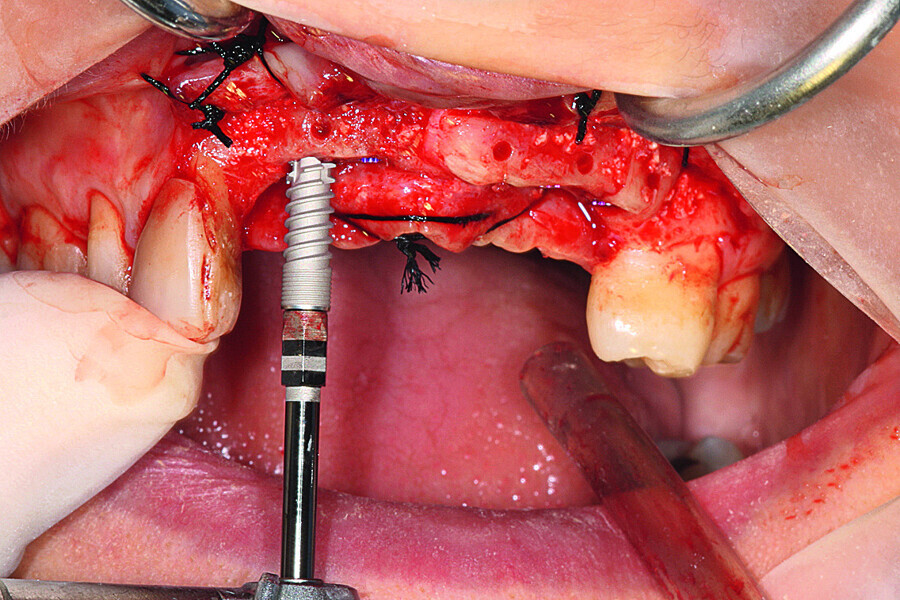

Fig. 15: Aadva self-tapping implants were placed.

Fig. 16: All five implants equipped with threaded cover screws and the surrounding tissue sutured.